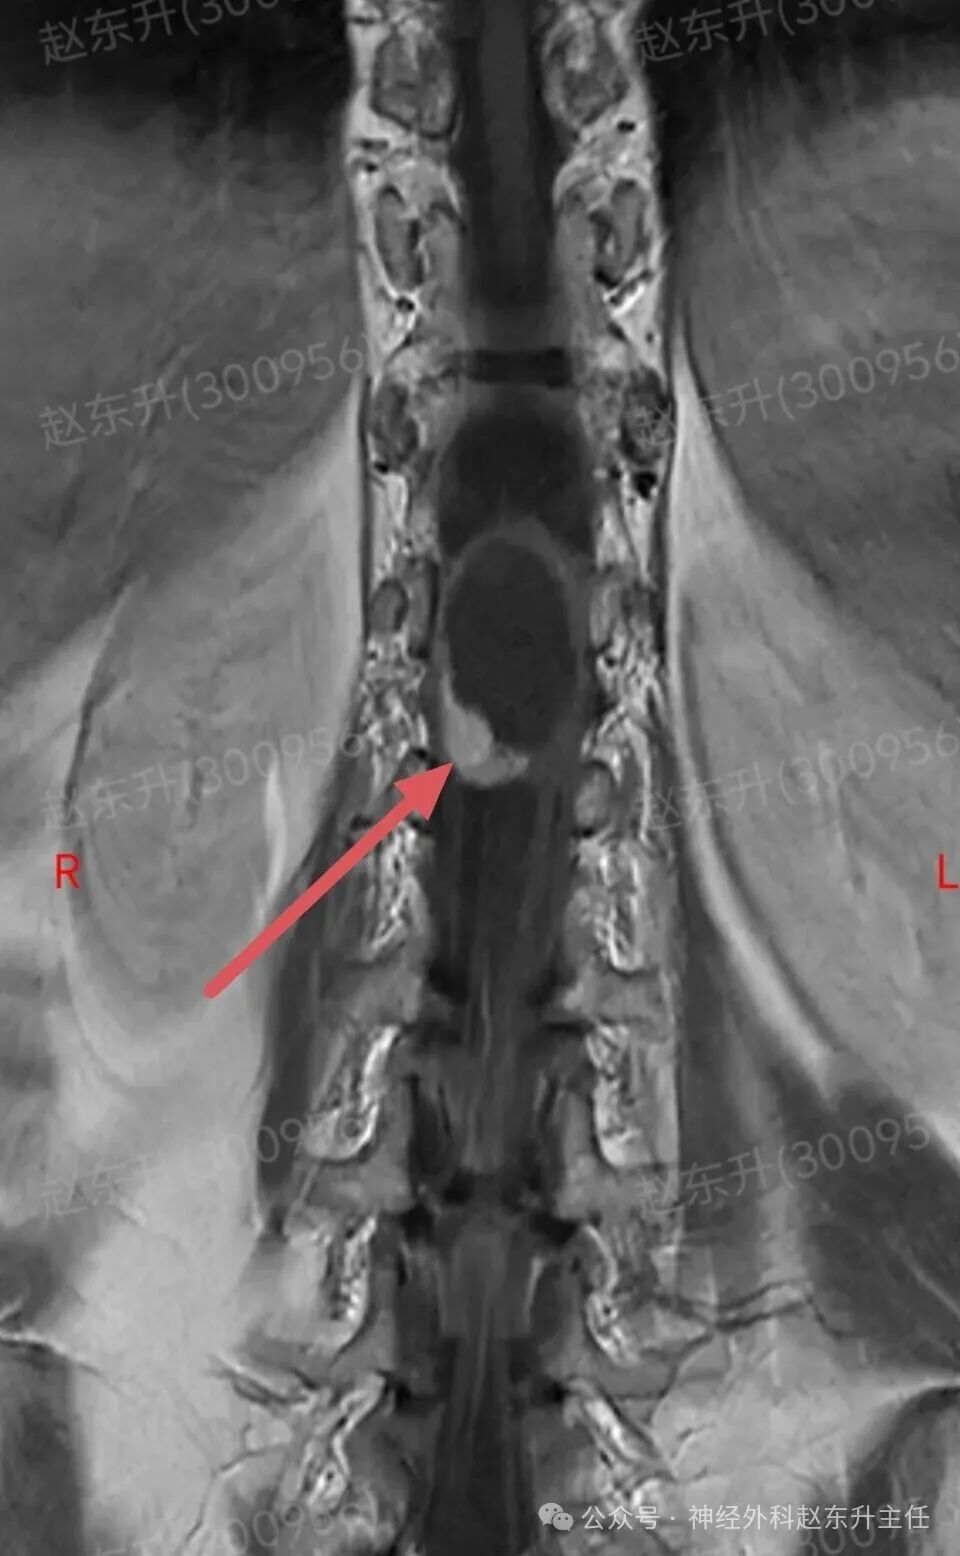

上周门诊来了一位58岁女性,患者因为下肢和腰背部顽固性疼痛半年,在各大医院就诊曾行针灸按摩,艾灸电疗等治疗没见缓解,而且疼痛评分可以达到8-9分,口服止痛药无效,康复理疗无效。随后查了一下腰椎磁共振,发现胸12腰1节段脊髓内异常信号,随后收入我科。入院之后查肌电图提示下肢和骶神经损伤严重,随后我们在全麻下使用显微镜,并且术中电生理监测下,给予脊髓内肿瘤次全切除,术后病理提示是胶质瘤。术后第2天我们就给他用了经颅磁刺激等神经康复治疗,虽然术后第1天右下肢肌力较术前减退,但经过10天的治疗以后,下肢肌力逐渐恢复,可以下地行走了。术后他还需要进一步的放疗和化疗来抑制肿瘤的生长,预防肿瘤复发。

图片图片图片图片图片图片图片图片切除的肿瘤图片术后病理西安市红会医院神经外科赵东升主任介绍:脊髓内胶质瘤是一种起源于脊髓实质内部的胶质细胞(即神经系统的“支持”细胞)的肿瘤。与脊膜瘤(位于脊髓外)的关键区别在于,它生长在脊髓内部,因此会浸润并破坏正常的脊髓神经组织核心特征:性质:涵盖从低级别良性到高级别恶性的完整谱系,但以低级别为主。位置:完全位于脊髓中央,可累及多个脊髓节段,甚至全长脊髓。特点:肿瘤与正常脊髓组织边界不清(浸润性生长),手术全切极为困难。其生长直接破坏神经传导束,导致严重神经功能障碍。发病率:相对少见,约占所有中枢神经系统胶质瘤的2-4%,但却是儿童最常见的髓内肿瘤。无明显性别差异。与脊膜瘤的关键区别总结

主要类型1.室管膜瘤(约占60%):常见的成人髓内胶质瘤。多为低级别(WHO I级和II级),生长缓慢。常发生于颈段和胸段,常有明确边界,有时可有“假包膜”,是手术全切希望最大的一种。2.星形细胞瘤(约占30%):常见的儿童髓内胶质瘤。从低级别(毛细胞型星形细胞瘤,WHO I级,预后好)到高级别(胶质母细胞瘤,WHO IV级,预后极差)都有。浸润性生长为特点,与正常脊髓几乎无边界,手术全切风险极高。3.其他少见类型:如血管母细胞瘤(常与VHL病相关)、少突胶质细胞瘤等。临床表现(症状)症状因肿瘤生长缓慢而隐匿、渐进性加重,早期易被忽视。典型症状:1.感觉障碍(最早、最常见):l分离性感觉障碍:这是特征性表现。由于肿瘤侵犯脊髓中央的白质前连合,导致痛觉、温觉纤维受损,而触觉、深感觉保留。患者表现为双侧对称性的、节段性的痛温觉减退或消失,而触觉正常l麻木、酸痛、束带感。2.运动障碍:n肿瘤平面以下出现肢体无力、僵硬、肌肉萎缩(尤以手部小肌肉萎缩常见)。n行走困难,步态不稳。3.疼痛:定位不明确的颈背部疼痛,夜间痛可能更明显。4.自主神经功能障碍(晚期):l大小便失禁或困难。l性功能障碍。l皮肤营养障碍(无汗、皮肤干燥等)。诊断增强磁共振(MRI): 是首选和确诊的关键检查。典型表现:可见脊髓呈梭形、偏心性或中心性增粗。肿瘤在T1像呈等或低信号,T2像呈高信号,增强后强化模式多样(可均匀、不均匀或环形强化)。可清晰显示肿瘤范围、有无囊变、脊髓空洞等。CT:价值有限,主要用于评估是否有脊椎骨质改变。治疗治疗远比脊膜瘤复杂,需在多学科团队(神经外科、肿瘤科、放疗科)指导下进行个体化综合治疗手术治疗(首要且核心):l目标:在最大限度保护神经功能的前提下,实现最大安全程度的肿瘤切除。全切是目标,但常因肿瘤边界不清而无法实现。l技术:在术中神经电生理监测(监测运动、感觉传导束功能)的保驾护航下,使用显微外科技术、超声吸引、激光等进行精细操作。功能保护优先于肿瘤全切放射治疗:主要适用于:高级别胶质瘤术后辅助治疗、无法全切的低级别胶质瘤术后残留、肿瘤复发无法再次手术者。化学治疗:l对于高级别(恶性)脊髓胶质瘤,可参照脑胶质瘤方案进行化疗(如替莫唑胺)。l对于部分复发的低级别胶质瘤也可能使用。预后与随访预后差异巨大,高度依赖于肿瘤的病理类型和分级l低级别室管膜瘤:若能实现全切,预后良好,可达到长期无进展生存,甚至临床治愈。复发率低。l低级别星形细胞瘤(如毛细胞型):全切后预后也很好。次全切后也可能长期稳定。l高级别胶质瘤(如胶质母细胞瘤)预后极差,即使积极治疗,也极易在脊髓内播散复发,生存期短。l随访:术后需定期(通常每3-6个月,后逐渐延长)进行增强MRI复查,监测肿瘤是否残留或复发。神经功能康复治疗至关重要赵东升主任简介医学硕士,西安市红会医院北院区神经外科主任医师,从事神经外科近20年。使用独创的“三维一体疗法”成功促醒大量昏迷病人,使上百例脊髓损伤瘫痪患者重新站起来。最早在陕西省开展第一例脊髓电刺激治疗昏迷病人,第一例脊髓电刺激手术治疗截瘫病人,第一例脊髓电刺激手术治疗下肢缺血顽固性疼痛。主编专著3部,参编专著11部,发表学术论文30余篇,荣获国家专利32项(其中四项发明专利),担任多部杂志编委及审稿专家。擅长:1.脑病方面:昏迷促醒,脑肿瘤、脑积水、脑梗死偏瘫、肌张力增高、顽固性癫痫、三叉神经痛、脑干出血、老年痴呆、帕金森、头痛等;2.脊髓病方面:脊髓损伤、脊柱术后疼痛、大小便障碍、脊髓肿瘤、脊髓空洞、小脑扁桃体下疝畸形、脊髓栓系、脊膜膨出、痉挛性截瘫等;3.周围神经疾病方面:糖尿病足、下肢缺血性疼痛、臂丛神经损伤、腓总神经损伤、腕管综合征、肘管综合征、男性功能障碍等门诊时间:北院区:周一全天门诊二楼203A  第五诊室南院区:周二全天门诊三楼310诊室